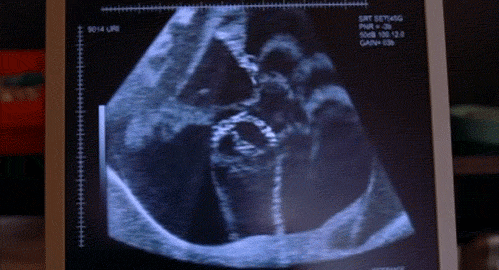

四维彩超检查是一项辅助检查,虽然彩超排畸检查清晰度很高,但受多方面因素影响,超声检查依然不能筛查出所有畸形

像胎儿的视力听力障碍、手指脚趾畸形、神经系统疾病和代谢疾病、水脑、侏儒症等问题是不在四维彩超检查范围内的。